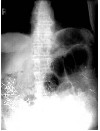

سهشنبه ۰۶ ژانویه ۲۰۰۹ - ۱۷ دی ۱۳۸۷ ماجرا از این قرار بوده که یک خانم محترم برای کشتن همسر گرامی خودشان از یک روش ابداعی بسیار جالب استفاده کرده اند. ایشان درون کپسول های دارویی را با میخ های ریز و سوزن های ته گرد پر می کرده و به شوهر بیچاره می خورانده است.